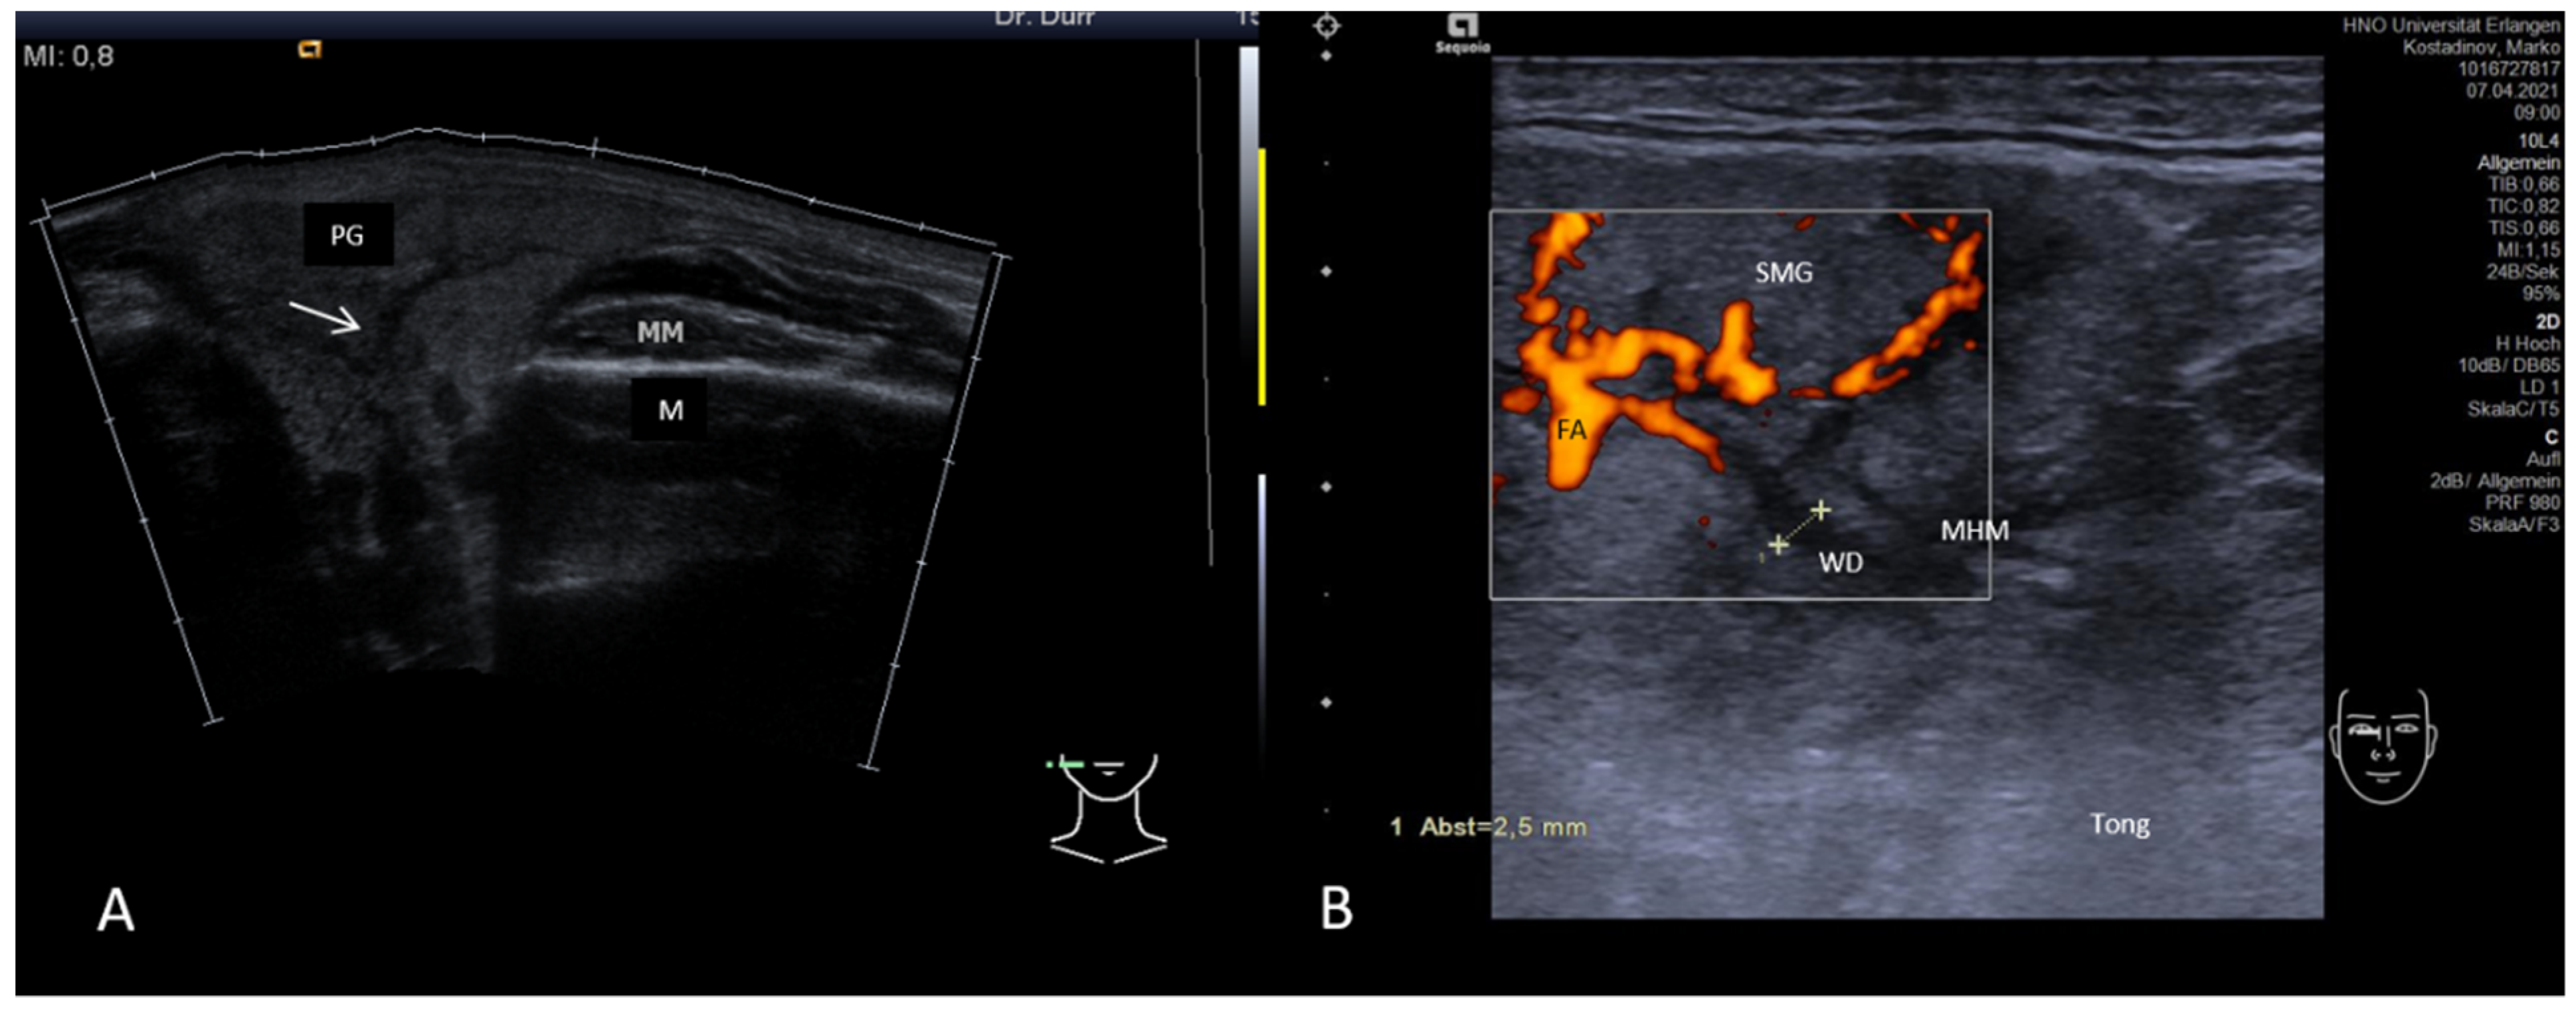

3.2. Findings in Normal Anatomy in Major Salivary Glands

3.3.2. Obstructive Sialadenitis Caused by Sialolithiasis

3.3.3. Non-Sialolithiasis-Caused Unspecific Sialadenitis with Sialodochitis and/or Duct Stenosis with Primary or Secondary Obstruction